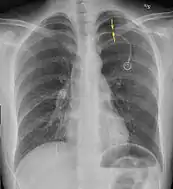

Anteroposterior inspired X-ray, showing subtle left-sided pneumothorax caused by port insertion

Chest X-ray showing a pneumothorax on the right (left in the image), where the absence of lung markings indicates that there is free air inside the chest

Chest X-ray showing the features of pneumothorax on the left side of the person (right in image)